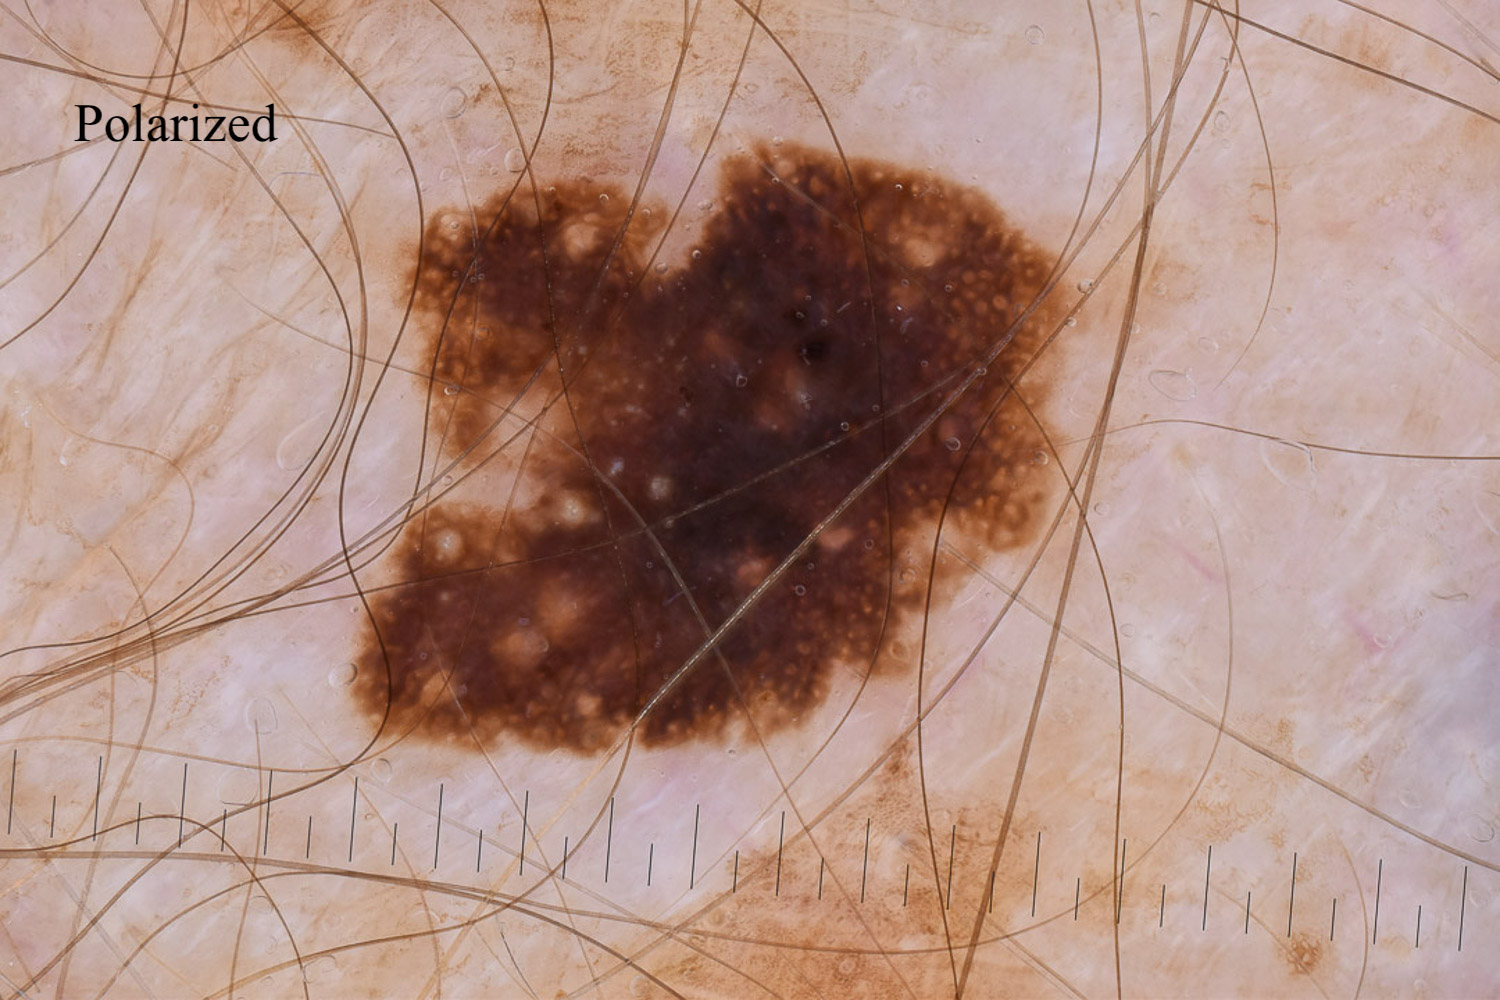

Case: 32